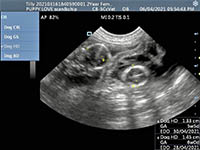

Mobile Ultrasound Pregnancy Scanning and Microchipping Services

Puppy Love scan and chip